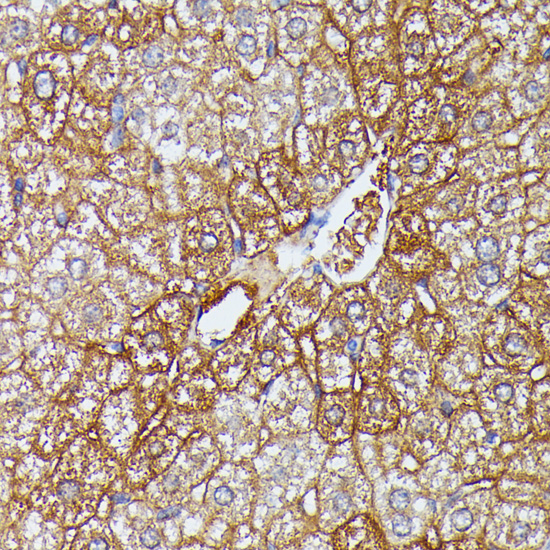

Immunohistochemistry of paraffin-embedded rat liver using HDLBP at dilution of 1:100 (40x lens).

Immunohistochemistry of paraffin-embedded human liver using HDLBP at dilution of 1:100 (40x lens).

Immunohistochemistry of paraffin-embedded mouse liver using HDLBP at dilution of 1:100 (40x lens).